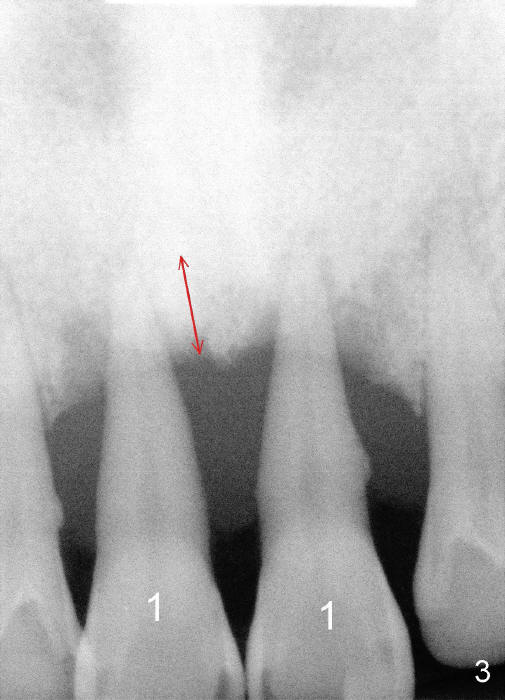

A 44-year-old man has advanced periodontitis (Fig.1,2). The infection resolves substantially 5 days post scaling & root planing (Fig.4,5). The two centrals have severe bone loss (Fig.3) and are going to be replaced by 5x20 mm implants (Fig.6).